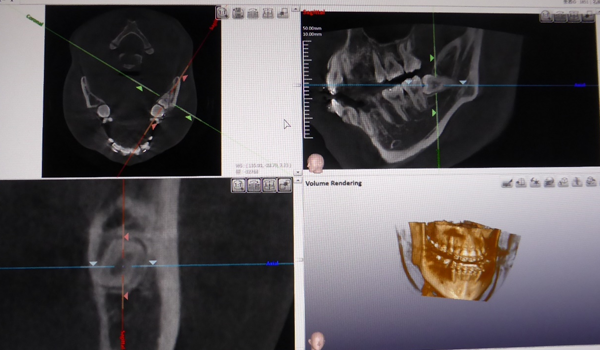

コンピュータを駆使しデータ処理と画像の再構成を行うことで、断層写真を得ることができる装置です。

歯科用CTとは、歯科に特化したCT装置で、コーンビームCTとも言われています。

歯科用CTとは、コーンビーム式のスキャンを行う事で、短時間のX線照射による、歪みの少ない繊細な画像を得ることができます。

抜歯

下の顎には太い神経と血管が走っており、特に下の親知らずの抜歯の時、傷つけないように注意が必要になります。

従来のレントゲンではこの太い神経・血管が鮮明に映らないことが多く、安全に抜歯するためにCTを撮影します。 また埋伏過剰歯を抜く場合にも使用します。

歯が骨の中に完全に埋もれている場合、正確に歯の位置を確認するためにCTを撮影します。